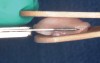

Fig 13. Fileting tissue to 1.5 mm thick utilizing a sandwich technique with saline-soaked tongue blades (Fig 13). Three grafts measuring 10 mm x 10 mm, 10 mm x 12 mm, and 10 mm x 15 mm were created from one tuberosity (Fig 14 and Fig 15).

Figure 13

Fileting can be accomplished freehand either on moistened gauze laid on a moistened sharpening stone for support, a moistened surgical towel, or a moistened tongue blade. If necessary, two tongue blades can be utilized with a "tong"-like grip to secure the CTG for fileting (Figure 13). The importance of preventing desiccation of the graft cannot be overemphasized.

The techniques for de-epithelialization and graft trimming with what the authors call the "book" or "butterfly" technique can be visualized in Figure 11 and Figure 12. When the initially harvested CTG is more than 7 mm thick it can be sliced further into one connected CTG in a "snake" or "trifold" configuration or separated into multiple individual CTGs to a 1 mm to 1.5 mm thickness (Figure 13 through Figure 15). In some instances when the tuberosity tissue forms a "c" shape distal to the molar, the CTG can be fileted and then placed around the buccal or lingual aspect of teeth to conform to the shape of the cementoenamel junction (CEJ) around single or multiple adjacent teeth (Figure 11 and Figure 12).